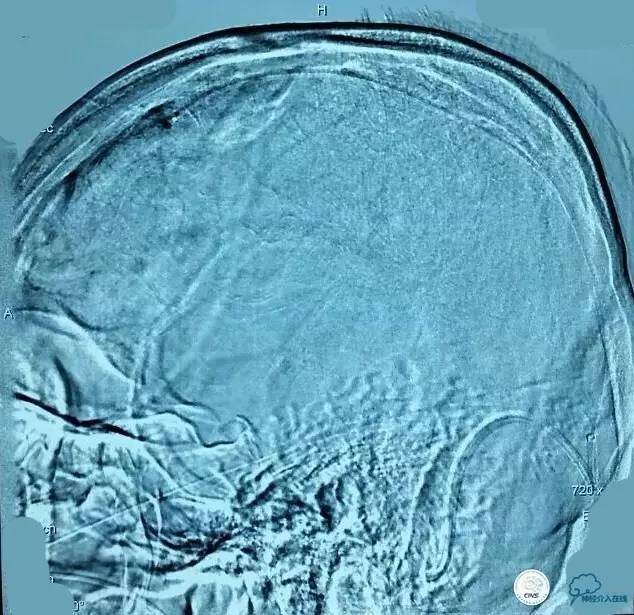

▼第三次取栓后造影,窦通畅,下矢状窦显影延迟,说明上矢状窦通畅了。

▼正位:

静脉窦血栓入路比动脉路径要困难的多,可以采用的手段以往主要是接触性溶栓、球囊扩张,手术往往要耗费大量的时间。随着介入器材的不断进步,我们配合中间导管、可回收支架取栓技术、接触性溶栓技术,大大提高了效率,提高了开通率,明显缩短手术时间。